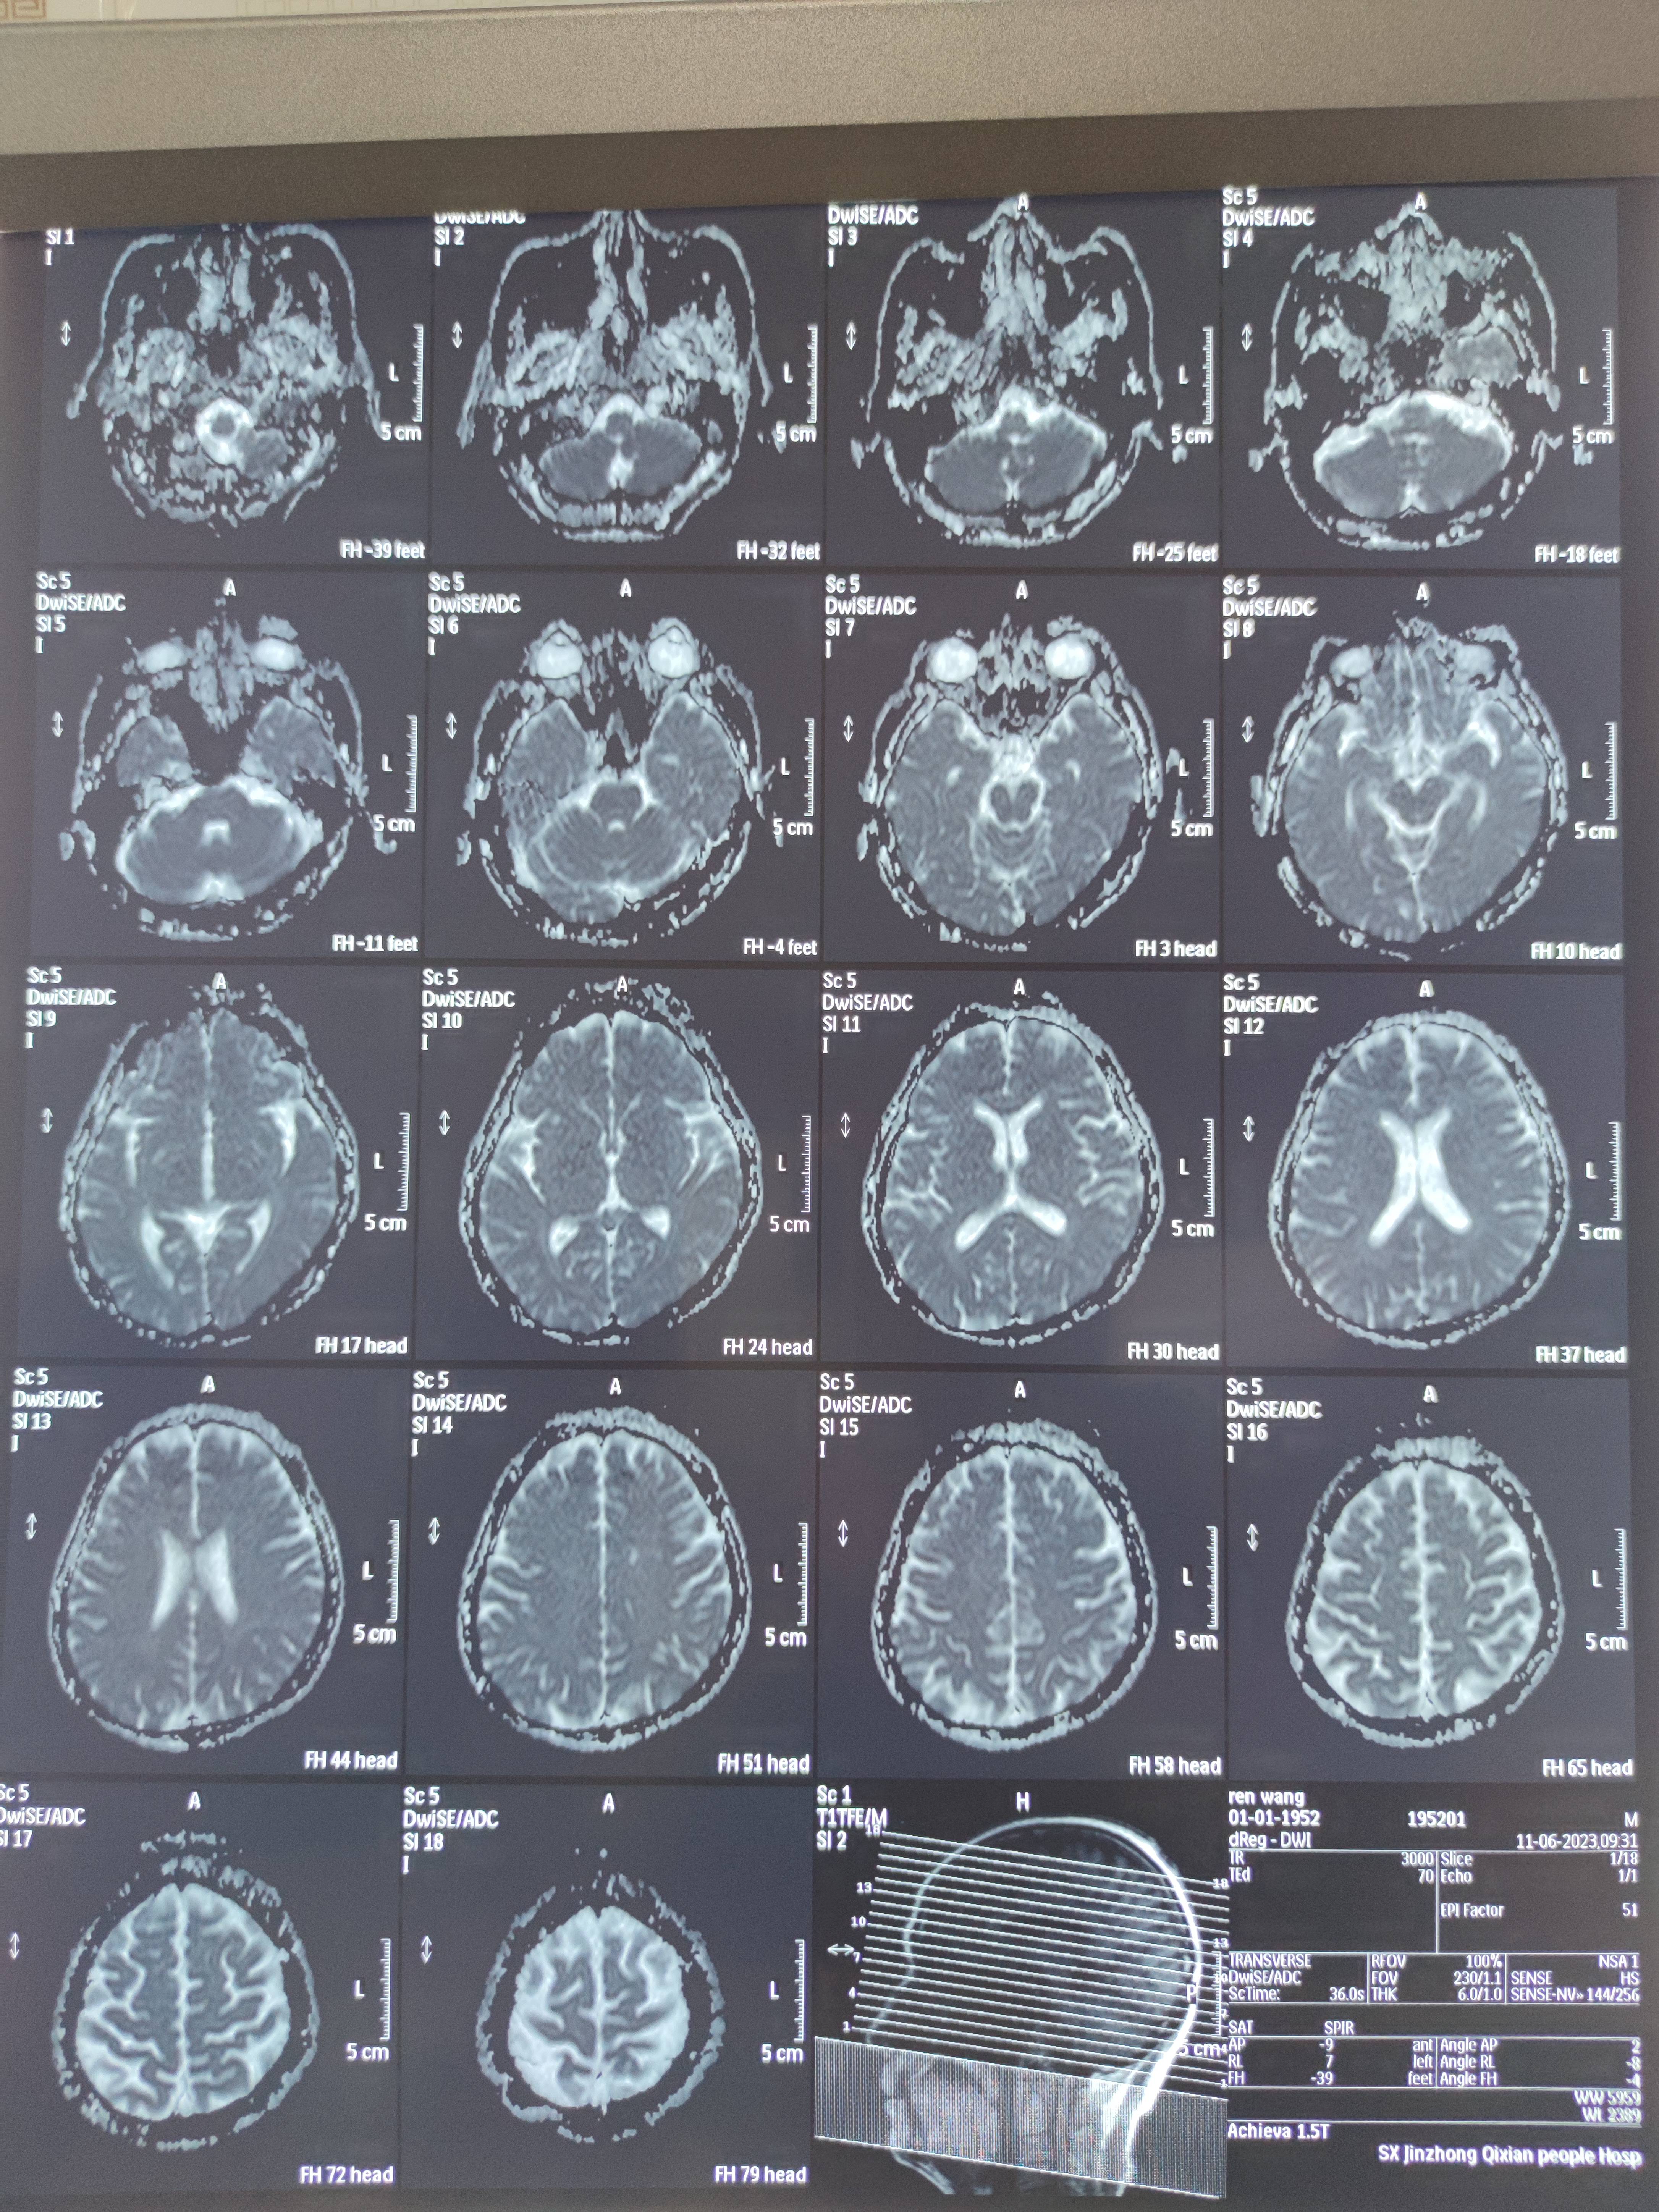

四月份癌胚抗原还是5.6,这个月到8了,持续升高。做了核磁增强,左侧桥小脑角哪有个地方不确定。肝脏核磁平扫弥散有两个点状高信号,转移也排不了,胃肠镜正常,左颈部有个变圆的淋巴结,保险点是不该加个化疗药了?咨询了陈波主任,等结果的吧!图片